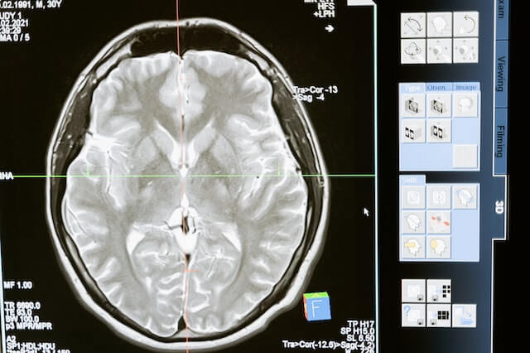

뇌졸증은 뇌혈관이 막히거나 터져서 뇌에 혈액 공급이 잘 되지 않아 생기는 질병으로, 세계적으로 사망률과 장애율이 높은 질병 중 하나입니다. 뇌졸증은 예방할 수 있고, 발생했을 때 적절한 대처법과 치료법을 알면 후유증을 줄일 수 있습니다. 이 글에서는 뇌졸증의 원인, 예방, 대처법, 치료법에 대해 간단하게 알아보겠습니다.

뇌졸증은 뇌의 혈류가 중단되어 뇌세포가 손상되는 질환으로, 매우 심각한 건강 문제이자 사망 원인 중 하나입니다. 뇌졸증을 예방하기 위해서는 원인을 정확히 이해하고 건강한 삶의 지침을 따르는 것이 중요합니다. 뇌졸증은 크게 두 가지 유형으로 나뉩니다. 허혈성 뇌졸중은 혈관의 혈전이나 혈전이 원인이고, 출혈성 뇌졸중은 혈관이 파열되어 뇌에 출혈이 생기는 것입니다. 이 두 가지 유형 모두 고혈압, 당뇨병, 흡연, 과체중 등의 원인이 있는 경우 발생할 확률이 높아집니다. 뇌졸증 예방을 위한 건강한 삶의 지침은 다음과 같습니다. 첫째, 정기적인 건강검진을 통해 고혈압, 당뇨병 등의 질병을 조기 발견하고 관리하세요. 특히 중년 이상의 경우, 고혈압의 발병률이 높아지므로 정기적인 검사가 필요합니다. 둘째, 건강한 식습관은 뇌졸증 예방에 중요한 역할을 합니다. 나트륨 섭취를 줄이고, 식이섬유와 불포화지방산이 풍부한 과실, 채소, 견과류 등을 섭취해야 합니다. 셋째, 꾸준한 운동은 뇌졸증 발생 위험을 낮춥니다. 꾸준한 심폐지구력 운동과 근력운동을 병행해 심혈관 기능을 향상시키고, 신체의 다양한 조절 기능을 유지하도록 하세요. 마지막으로, 흡연 및 과도한 음주는 뇌졸증 발생 위험을 높입니다. 금연하고 적당한 음주로 건강한 생활을 지속하시길 권장합니다. 앞서 언급한 건강한 삶의 지침을 따르면 뇌졸증의 위험을 줄이고, 건강하고 안전한 삶을 영위할 수 있습니다. 자주 확인하고 실천하여 뇌졸증 예방에 힘이 되시길 바랍니다.